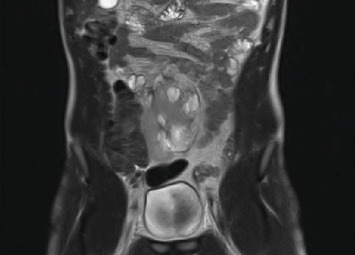

肾盂输尿管连接处梗阻(UPJO)见于约30%的异位肾患者。由于狭窄的骨盆空间和损伤异常结构的风险,异位盆腔肾UPJO提出了一个独特的治疗挑战。大多数使用机器人手术系统治疗盆腔异位肾UPJO的经验是基于儿科人群的。只有少数案例成功的机器人辅助手术在成人患者与这种情况已被描述。本病例报告表明,机器人辅助UPJO手术的适应症可以安全地扩展到包括骨盆异位肾的复杂成人病例。

Ureteropelvic junction obstruction (UPJO) is observed in approximately 30% of patients with ectopic kidneys. Due to the narrow pelvic space and risk of injuring aberrant structures, an ectopic pelvic kidney with UPJO presents a unique treatment challenge. Most experiences in treating UPJO in pelvic ectopic kidneys using robotic surgical systems are based on the pediatric population. Only a few cases of successful robotic-assisted surgery in adult patients with this condition have been described. This case reports illustrates that the indications for robotic-assisted surgery for UPJO may safely be expanded to include complex adult cases with pelvic ectopic kidney.